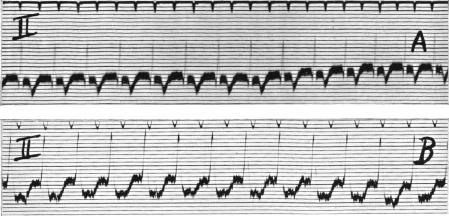

Campbell M, Elliott G A

Cardiographic Department, Guy's Hospital, and the National Hospital for Diseases of the Heart.

Br Heart J. 1939 Apr;1(2):123-60. doi: 10.1136/hrt.1.2.123.